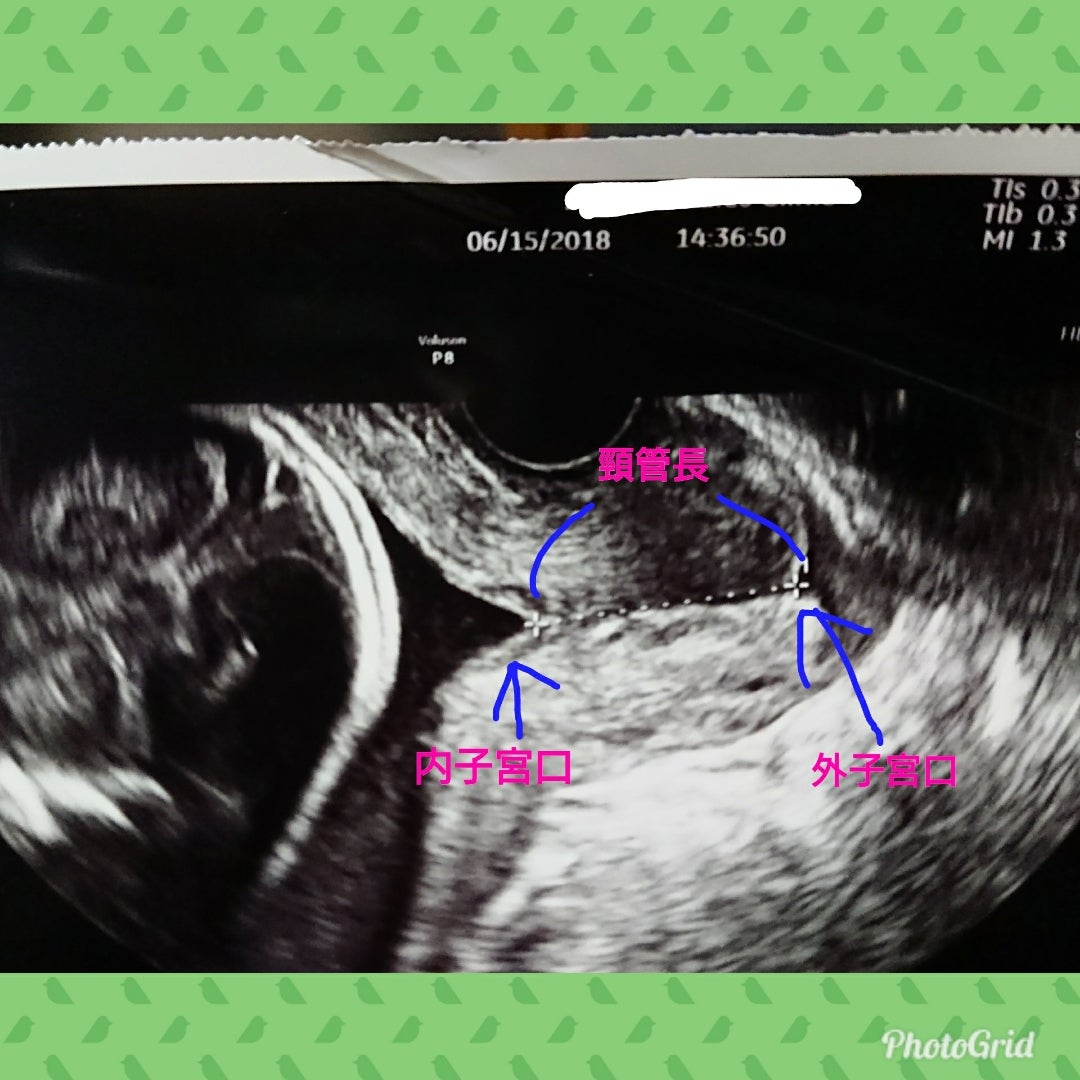

03 妊娠中期: ₀₉₎切迫早産 頸管長、子宮口開大度、胎児下降度–飯能産婦人科 ,医学情報。

いそいち産婦人科医院LC子宮頸管長の計測・子宮頸管の観察。